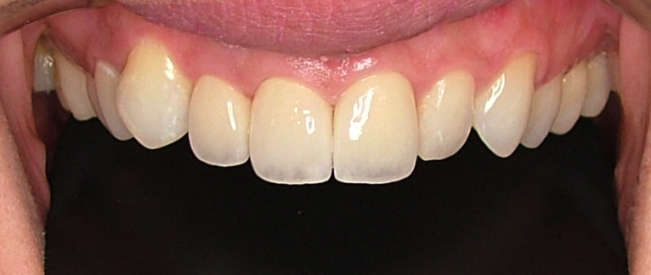

| 治療内容 | ジルコニアセラミック |

|---|---|

| 治療回数 | 4回 |

| 治療時の費用 | 660,000円(税込) ※本症例当時の価格です。最新の費用はこちら |

| リスク・副作用 | 乱暴なブラッシングをすると歯肉が退縮する可能性があります。 |